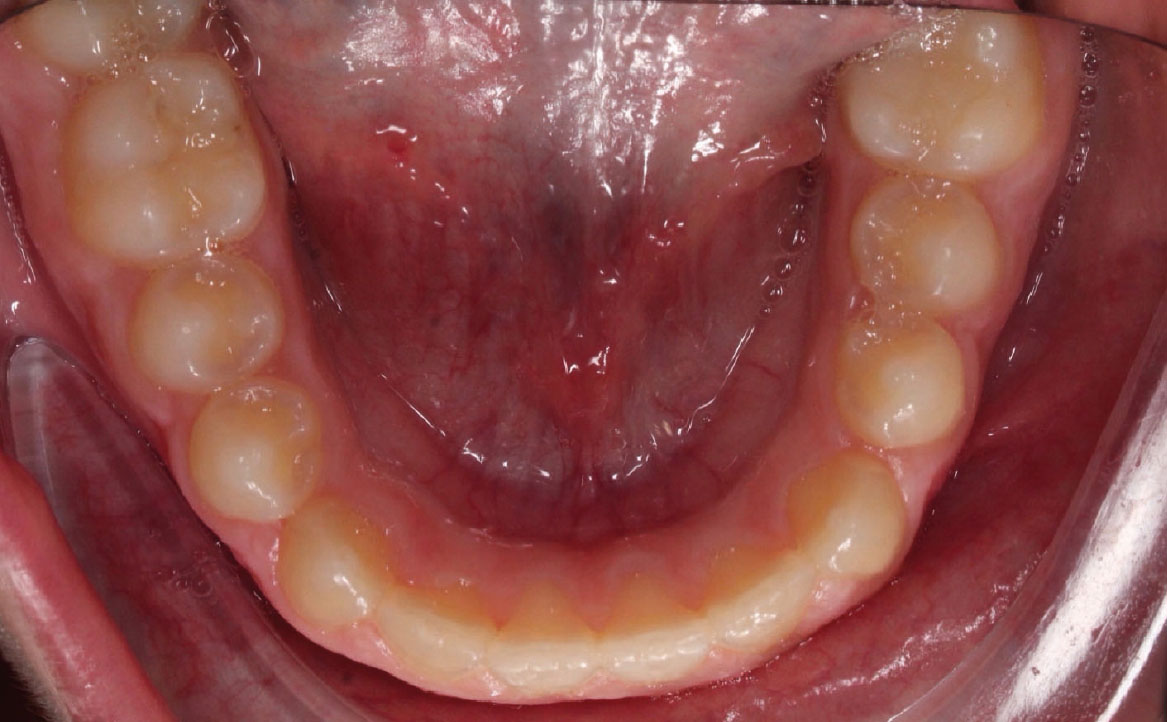

Fig. 7A Foto dell'arcata inferiore.

L’overjet e l’overbite sono entrambi ridotti in massima intercuspidazione. Trasversalmente il mascellare superiore è contratto (fig. 4-7).

All’esame obiettivo si osserva prima classe molare bilaterale e classe canina non valutabile poiché il paziente si trova in fase di dentizione mista con permuta in atto degli elementi dentari decidui. L’analisi cefalometrica evidenzia Ia classe scheletrica tendente alla III, ipodivergente. Dal primo contatto alla massima intercuspidazione si rileva la presenza di uno shift mandibolare che determina uno scivolamento mandibolare anteriore: ne risulta overjet negativo e overbite ridotto. La postura linguale del paziente è anteriore e la deglutizione atipica. Sul piano trasversale è osservabile una contrazione del mascellare.